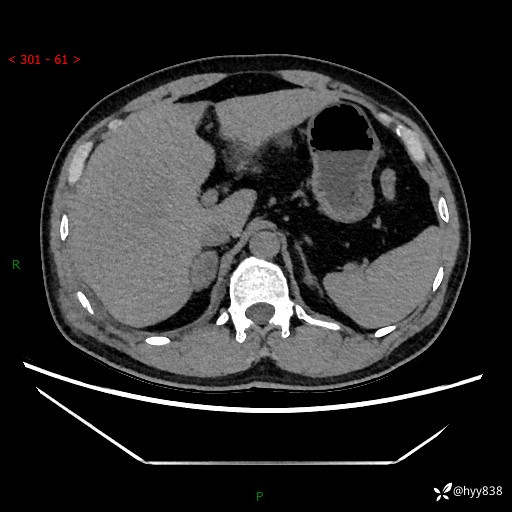

现病史:患者9月4日摔伤在深圳市宝安区中心医院行CT检查提示右侧肾上腺区结节(38*27mm),复查B超提示右侧肾上腺区可见一61*24mm异常低回声团,建议进一步检查。进一步完善增强CT后提示:右侧肾上腺区肿块及周围渗出改变,大致同前,考虑肾上腺腺瘤,不除外瘤内出血可能,否认阵发性头晕、头痛、出汗、乏力等不适,门诊以“ 右侧肾上腺肿瘤”收入住院。 起病来,患者精神、食欲、睡眠可,大便通畅,小便如上述,体力体重无明显改变。

肾上腺CT平扫

增强(动脉期+静脉期)